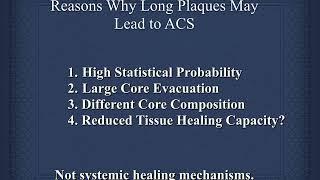

What are vulnerable plaque which lead to ACS?#ACS,#vulnerable,#plaque,#PCI,#rupture,#OCT,#cardiology

Mark Brezinski MD,PhD,CPT

156

519

5 лет назад